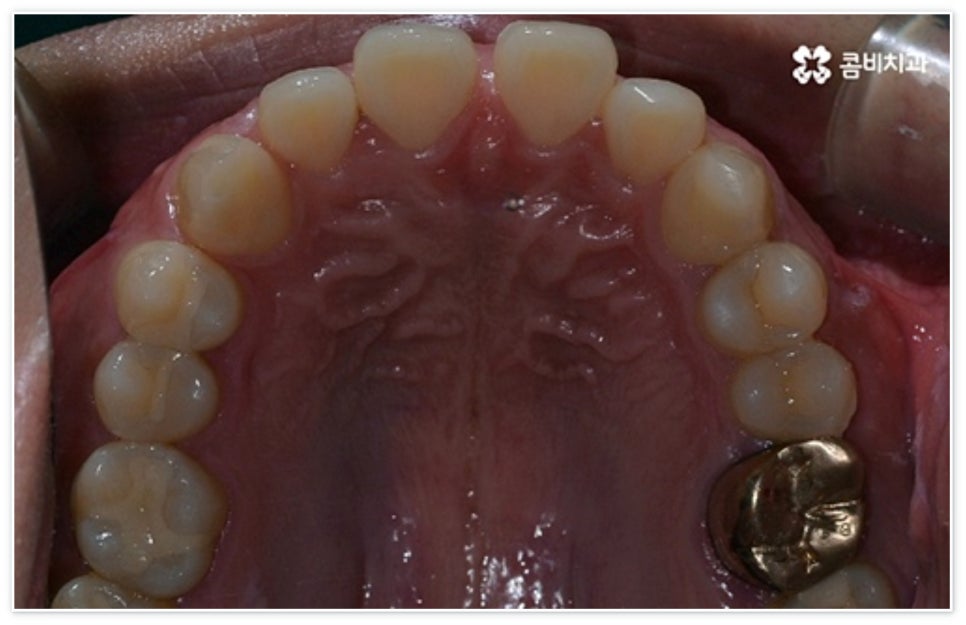

벌어진 앞니 사이가 넓지 않을 때는 간단하게 레진으로 수복할 수 있어요. 레진 수복 치료는 치아 색상의 재질을 이용하기 때문에 심미성이 좋으며 빠른 수복 (보통 당일 치료) 이 가능한 방법이지만 시간이 오래 지나면 결과물에 변색이나 마모가 일어날 수 있다는 단점을 가지고 있고, 치료 후 치주질환으로 잇몸이 내려가거나 틈이 추가로 발생할 경우 음식물이 끼면서 2차적인 문제가 발생할 수 있습니다. 증상에 따라 레진 대신 무삭제 라미네이트를 선호하시는 분들도 계시고, 만약 치료 범위가 크거나 이미 치아 사이에 충치 등 구강 질환이 발생하여 삭제량이 많을 때는 라미네이트 또는 올세라믹 크라운과 같은 보철 수복 치료를 해 주는 것이 더 적합한데, 이때 치아를 신중하게 깎아내어 손상을 최대한 줄이면서 모양이나 크기, 잇몸 라인 등을 종합적으로 고려하여 꼭 맞는 보철물을 자연스럽게 붙이는 것이 중요하기 때문에 환자분들의 만족도를 높이기 위해서 의료진의 높은 숙련도나 세심한 기술력이 요구되는 치료 방법이라고 할 수 있어요.

앞니 벌어짐 이 외모에 큰 영향을 주는 문제이다 보니 기능적인 해결도 중요하지만 아무래도 심미성 회복에 보다 중점을 두게 되기 때문에 보철물 재질을 고를 때도 기존 자연 치아와 색조, 투명도 등을 자연스럽게 맞출 수 있는 올세라믹이나 지르코니아를 선호하시는 분들이 많이 있습니다. 이외에도 다양한 재질이 있으니 장단점을 꼼꼼하게 살펴보시고 담당의 선생님과 충분한 상담 후에 자신의 상황에 가장 잘 맞는 것으로 선택하시길 바라며, 이때 자체 기공소를 갖추고 있어 보철물을 제작할 때 의료진과의 빠르고 긴밀한 협조가 가능한 치과라면 환자분들의 불편을 덜어드리는 데 좀 더 도움이 될 테니 이 점도 한 번 체크해 보시길 권유드리고 있어요.

환자분들에 따라 다르지만 통상적으로 전체 교정이 1년에서 2년 반 정도 소요된다면 부분 교정은 6~8개월 정도로 기간 단축이 가능하여 치료에 대한 부담을 줄일 수 있으며 대부분 발치 과정 없이 필요한 부위에만 브라켓을 부착하는 만큼 불편함이 적고 구강 관리도 용이한 편이니 (사진에서 살펴볼 수 있는 케이스) 이에 대해서 자세히 알아보시면 좋을 거예요. 물론 누구나 가능한 것은 아니고 개인의 구강 상태에 따라 진행을 해야 하므로 꼼꼼한 검진과 충분한 상담부터 받아보시길 권유드리고 있습니다.